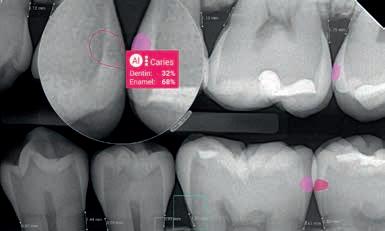

I DENNE SYSTEMATISKE GENNEMGANG samarbejdede

forskere fra Canada, Schweiz og Tyskland om at undersøge, hvor god kunstig intelligens (AI) var til at opdage carieslæsioner på kliniske intraorale fotos.

Ud af 3.410 potentielle studier blev 19 studier inkluderet fra databaserne Embase, Medline og Scopus. Seks af studierne havde lav risiko for bias, mens syv af studierne havde få problemer med anvendeligheden for alle domæner.

AI-modellernes præcision varierede markant med F1-scorer for hhv. klassifikation og detektion mellem 68,3-94,3 % og 42,8-95,4 % afhængigt af kameratypen: professionelle kameraer (68,3-95,4 %), intraorale kameraer (78,8-87,6 %) og smartphones (42,8-80 %). Kun et begrænset antal studier omfattede evaluering af carieslæsionernes sværhedsgrad.

Resultaterne viser, at objektiv detektion af carieslæsioner med AI har potentiale til at understøtte den kliniske diagnose, facilitere patientkommunikationen og muliggøre teletandpleje.

Fremtidige undersøgelser bør fokusere på at skabe mere robuste studiedesign, standardiserede målepunkter og inkludere evaluering af carieslæsionernes sværhedsgrad for at optimere anvendelsen af AI i klinisk praksis.

Moharrami M, Farmer J, Singhal S et al. Detecting dental caries on oral photographs using artificial intelligence: a systematic review. Oral Dis 2024;30:1765-83.